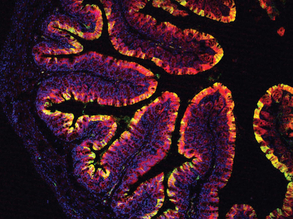

Gastric Rings

Cabbages for Colons